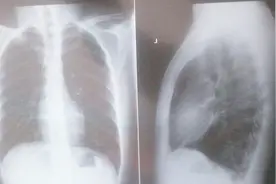

2、气胸

气胸,即气体进入了胸膜腔造成的疾病。它主要与胸部、肺部损伤有关。

气胸发生时,患者常常会感到突然的胸痛。与此同时,很多患者还会出现胸口发闷,有刺激性的咳嗽。还有少部分患者会出现刀割、针刺一般的异样感觉。

气胸多半发生在腹压剧烈变化时。例如举重、提重物、屏气排便、剧烈咳嗽时。此外,如果肺部组织病变出现破损,也可能导致这一问题。